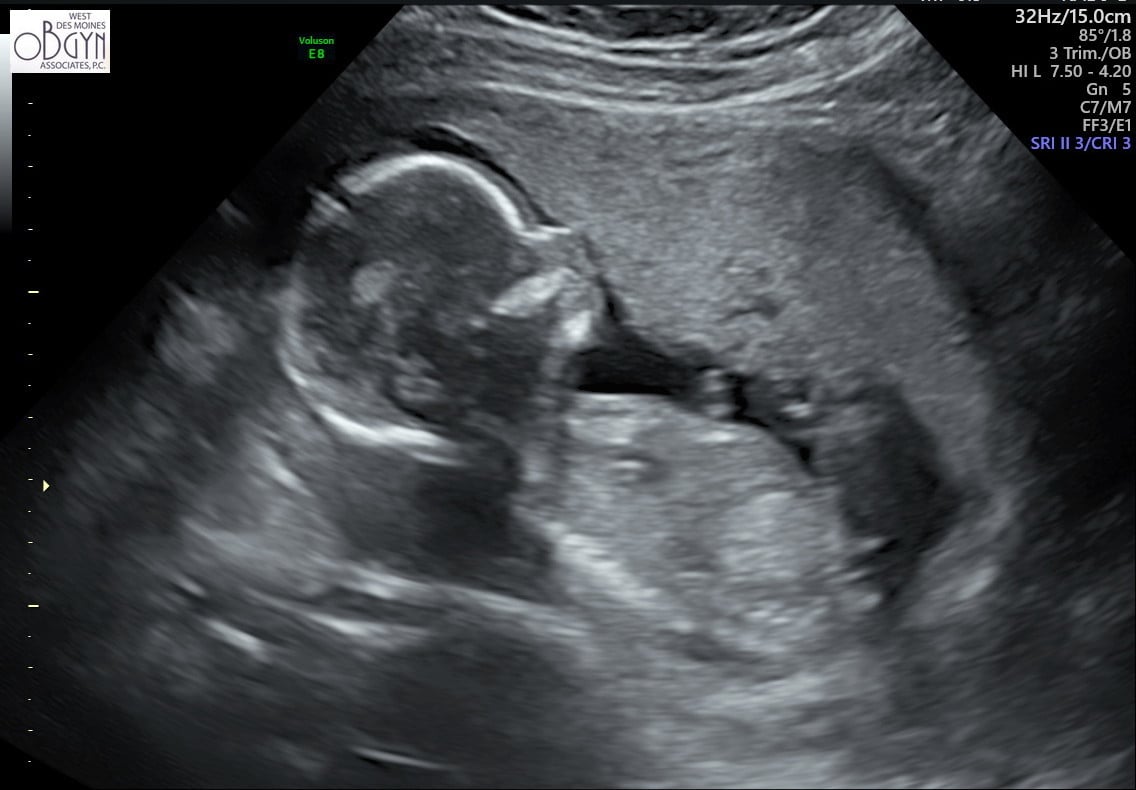

My NT went well.. baby measuring at 12 weeks 2 days exactly and I am 12 weeks 2 days! Saw the nose, the neck was normal, legs and arms.. have a video of him/her moving